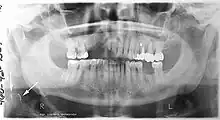

A panoramic radiograph of a 9 year old in mixed dentition